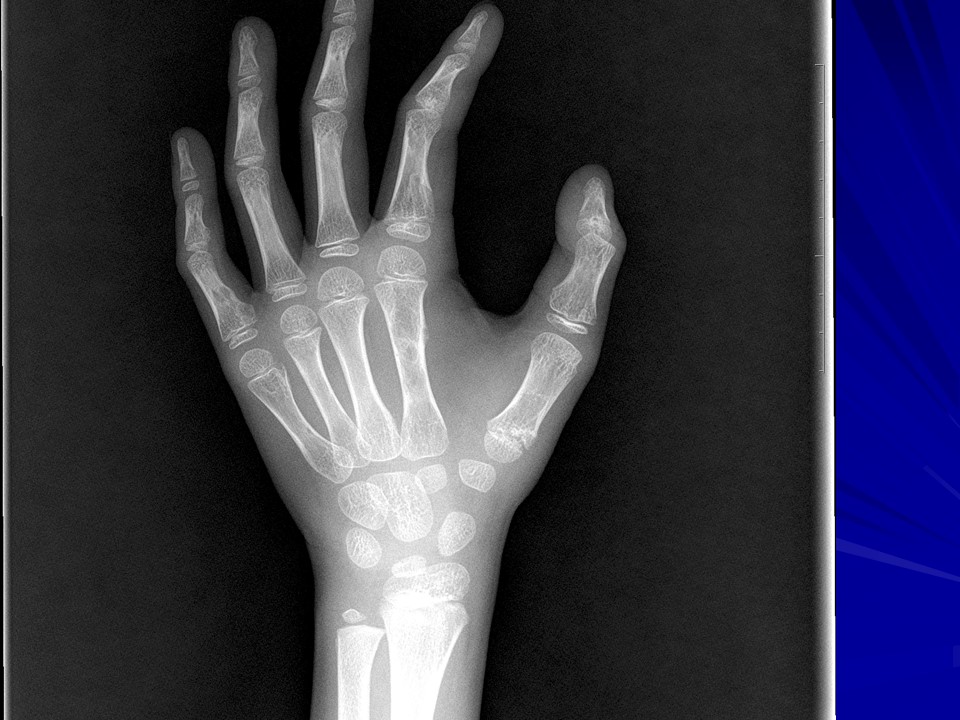

“常见骨肿瘤的X线诊断” 的相关文章